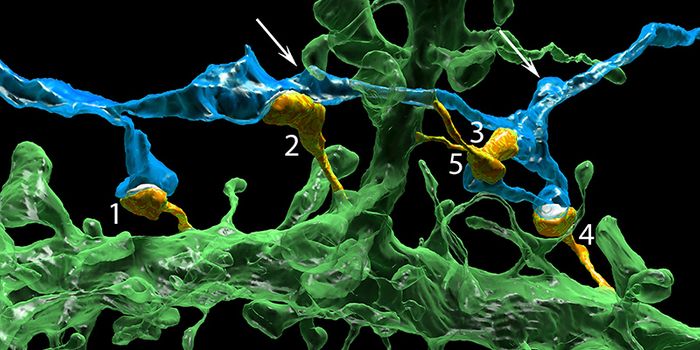

APR 27, 2015Cell & Molecular BiologyEvery time you make a memory, somewhere in your brain a tiny filament reaches out from one neuron and forms an electroch ...

MAY 24, 2016NeuroscienceAt the Max Planck Florida Institute of Neuroscience (MPFIN), researchers are looking at a a method used to repair DNA in ...